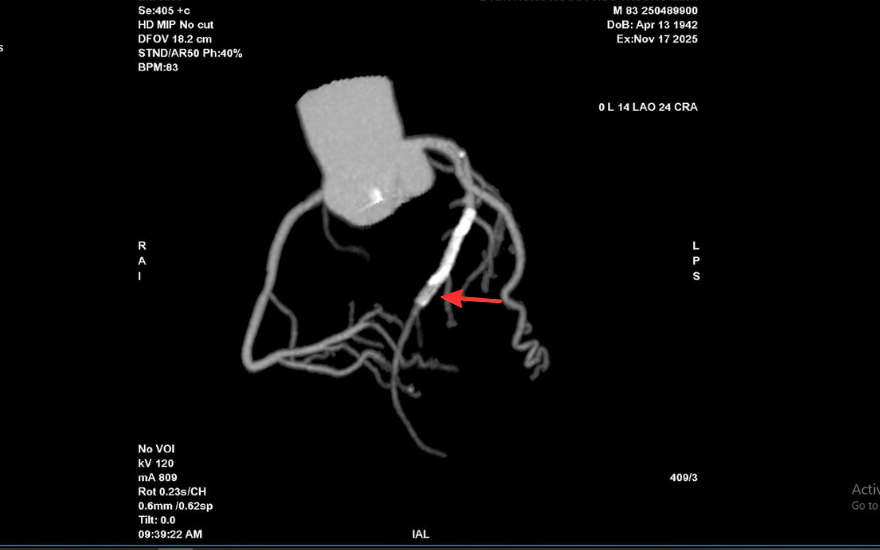

Tại BVĐK Hồng Ngọc, kết quả chụp CT 2560 lát cắt cho thấy tình trạng nghiêm trọng hơn nhiều so với biểu hiện ban đầu: mảng xơ vữa lan rộng gây hẹp nặng đoạn đầu động mạch liên thất trước và gần như làm tắc hoàn toàn lòng stent cũ. Đây là dấu hiệu cho thấy nguy cơ biến chứng tim mạch cấp tính có thể xảy ra bất cứ lúc nào nếu không được can thiệp kịp thời.

Vị trí hẹp khít trong lòng stent cũ của ông T trên hình chụp CT mạch vành 2560 lát cắt